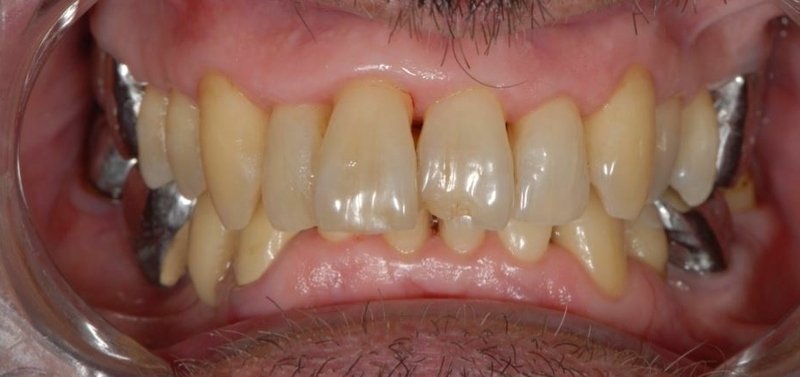

Cas 1 - Parodontie

Avant